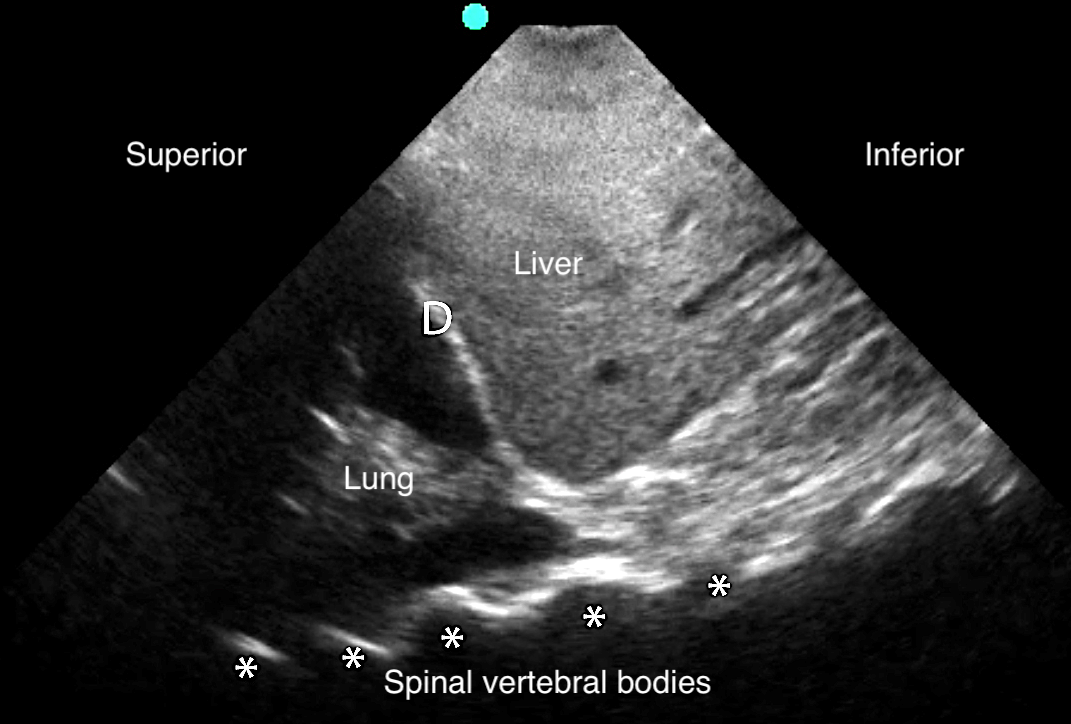

Pleural Effusion

- Anechoic space between parietal and visceral pleura78

- Normal air-filled lung is replaced by liquid-dense effusion, which now allows propagation of sound waves.

- Figure 18. Pleural effusion with spine sign

- Sinusoid sign: represents movement of lung within the effusion22

- Figure 20. Sinusoid sign

- Demonstrates fluctuating distance between visceral and parietal pleura during respiratory cycle